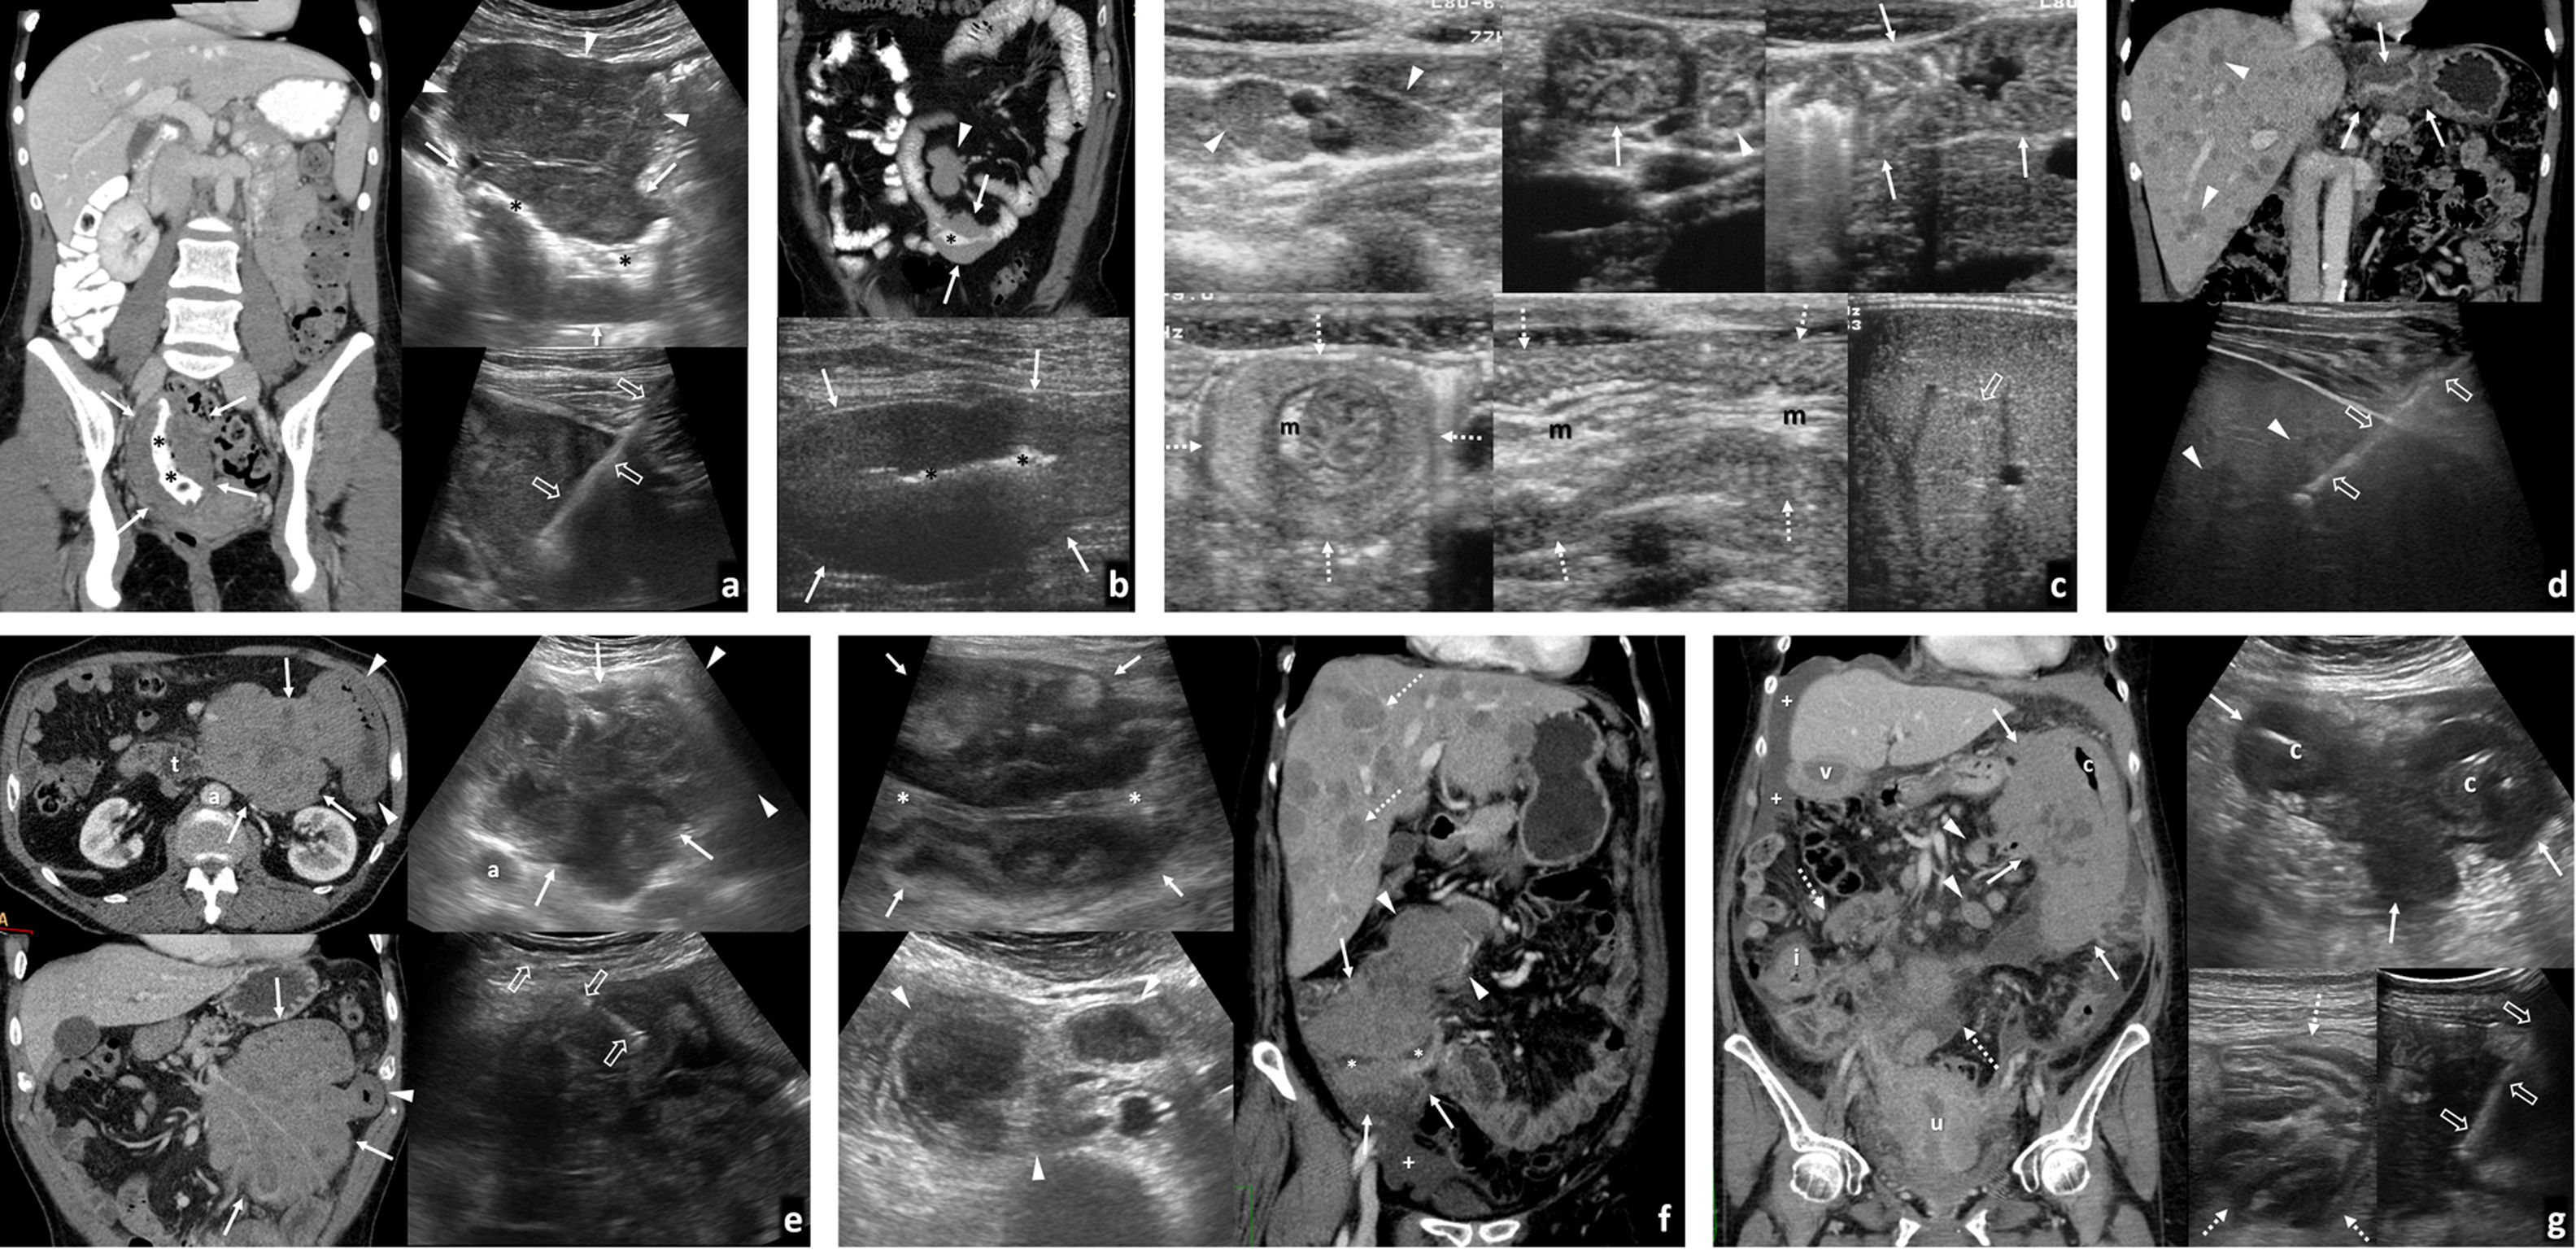

PancolitisClostridium difficileSu incidencia y gravedad está aumentando por el empleo de antibióticos de amplio espectro. La presencia de un engrosamiento muy marcado de la pared de todo el colon (puede limitarse a una afectación segmentaria), si bien no es exclusivo y puede no aparecer, orienta el diagnóstico, que se confirma con la detección de toxinas en heces y coprocultivo. Se ha descrito afectación del intestino delgado. Ecográficamente hay un aumento del espesor de la capa submucosa (hiperecogénica), con una muscular (hipoecoica) de espesor normal (fig. 4). Se han descrito imágenes hiperecogénicas en la luz que pueden indicar la presencia de membranas. La afectación pericolónica es desproporcionadamente escasa. Con frecuencia se acompaña de ascitis25. Puede progresar a un cuadro de megacolon tóxico con elevada morbimortalidad.

Afectación infecciosa del colon. A y B) Colitis pseudomembranosa. A) Imágenes de estudio ecográfico en paciente con diarrea sanguinolenta que muestra un colon (c) con marcado engrosamiento de la pared (flechas) y pliegues mucosos internos prominentes e irregulares (cabezas de flecha). Hay ascitis discreta (*). B) Reconstrucción coronal de estudio de tomografía computarizada (TC) en otro paciente con el mismo diagnóstico, donde apreciamos un importante engrosamiento de la pared del colon izquierdo, con predominio de edema en capa submucosa (*) y realce de la mucosa (cabeza de flecha), característicamente en esta patología con un mínimo compromiso del mesenterio adyacente. C y D) Colitis isquémica. Imágenes de ecografía (C) donde se visualiza la pared del colon izquierdo anormalmente engrosada con pérdida de la estratificación normal. En el estudio Doppler no es posible detectar la presencia de flujo en su interior a pesar de emplear el Power color o Doppler potencia, mucho más sensible a la detección de flujo lento. Vemos en la imagen axial del estudio de TC (D), realizado sin contraste por deterioro de la función renal del paciente, el engrosamiento de la pared del colon sigmoide (+), que se acompaña de importante trabeculación de la grasa mesentérica (flechas finas), hallazgos que suelen aparecen en la fase de reperfusión tras una isquemia mesentérica oclusiva o no oclusiva. Figura 4a cortesía del Dr. T. Ripollés (Valencia).

PeritoneoLa peritonitis tuberculosa es la manifestación más frecuente de la tuberculosis abdominal. Clásicamente se describen tres patrones: peritonitis húmeda, la más frecuente (90%), con ascitis de distribución libre o loculada, punteado ecogénico por alta densidad del líquido y engrosamiento peritoneal (fig. 3C); peritonitis seca, con escasa cantidad de líquido y adherencias completas o incompletas; y peritonitis fibrótica, con nódulos y masas mesentéricos y engrosamiento nodular del omento. La ecografía permite explorarlos con detalle y sirve de guía para la biopsia diagnóstica (fig. 3D). Descrita como la gran imitadora, su diagnóstico diferencial incluye la carcinomatosis peritoneal, el linfoma, la enfermedad de Crohn, el mesotelioma, el pseudomixoma peritoneal o la peritonitis piógena.

La peritonitis piógena (fig. 3E) es el resultado de la complicación de una infección abdominal generalmente de origen intestinal y puede derivar en abscesos, que a menudo requieren drenaje percutáneo guiado por ecografía. La peritonitis bacteriana espontánea es una complicación de cirrosis descompensada, a sospechar en caso de ascitis con fiebre o deterioro clínico. Su diagnóstico precisa paracentesis diagnóstica ecoguiada. Cabe mencionar las peritonitis parasitarias, que en nuestro medio suelen deberse a la rotura de un quiste hidatídico hepático (fig. 3F y G)32,33.

Tumores hematológicos (fig. 7)Aunque infrecuentes (1-8%), el tracto gastrointestinal supone el asiento extraganglionar más habitual del linfoma, casi siempre no Hodgkin-B, primario o secundario. El orden de frecuencia de afectación es estómago, intestino delgado (especialmente íleon distal), colon-recto y esófago. Ecográficamente suele presentarse como masa o, más habitualmente, un engrosamiento mural circunferencial hipoecogénico marcado, más homogéneo, largo y menos obstructivo que el carcinoma, en ocasiones preservando relativamente la estructura en capas. Puede ser multifocal, ulcerarse, cavitar y, por destrucción del plexo mioentérico, producir dilatación aneurismática de la luz. Suele acompañarse de adenopatías hipoecogénicas prominentes, y a veces de afectación peritoneal o de otros órganos. Con contraste muestra realce homogéneo, más discreto y tardío que otros tumores36,59,60.

Linfomas gastrointestinales. A) Linfoma difuso de células grandes de íleon terminal. Mujer de 36 años. Imagen izquierda: tomografía computarizada (TC) coronal con contraste oral e intravenoso. Imagen derecha: ecografía. Engrosamiento mural hipoecogénico e hipovascular marcado en un tramo largo de íleon distal (flechas) cuya luz se encuentra dilatada (*). Se acompaña de una masa mesentérica adyacente de ecogenicidad similar (cabezas de flecha), sobre la que se realizó BAG guiada ecográficamente (flechas huecas). B) Linfoma difuso de células grandes de yeyuno distal. Varón de 70 años. Imagen superior: TC coronal con contraste oral e intravenoso. Imagen inferior: ecografía. Engrosamiento mural hipoecogénico e hipovascular marcado en un tramo más corto de yeyuno distal (flechas), también con dilatación aneurismática (*) y una masa mesentérica adenopática acompañante (cabeza de flecha). El diagnóstico se consiguió con la biopsia percutánea del engrosamiento intestinal (no mostrado). C) Enfermedad inmunoproliferativa de intestino delgado (o “linfoma mediterráneo”, subtipo de linfoma extranodal de la zona marginal). Varón de 17 años con diarrea, fiebre y dolor abdominal. La ecografía muestra adenopatías mesentéricas homogéneas (cabezas de flecha), engrosamiento de pliegues de yeyuno proximal (flechas), con una invaginación larga de yeyuno (flechas discontinuas) con mesenterio en su interior (m), así como pequeñas lesiones focales hepáticas hipoecogénicas (flechas huecas). El diagnóstico se obtuvo con la biopsia de dos lesiones focales hepáticas (no mostrado). D) Linfoma T gástrico de alto grado asociado a enteropatía. Varón de 61 años con diagnóstico de enfermedad celiaca. Imagen superior: TC. Imagen inferior: BAG guiada ecográficamente. Engrosamiento circunferencial hipovascular e hipoecogénico (no mostrado) de antro gástrico (flechas), con múltiples lesiones focales hepáticas hipocaptantes (cabezas de flecha) y levemente hipoecogénicas. En la gastroscopia se ve una lesión antral ulcerada, pero las biopsias son repetidamente negativas. El diagnóstico se consigue con la biopsia percutánea de las lesiones hepáticas. E) Linfoma folicular de bajo grado de yeyuno proximal. Varón de 73 años. Imagen izquierda: TC axial (superior) y coronal MIP fino (inferior). Imagen derecha: ecografía, corte transversal (superior) y biopsia percutánea. Engrosamiento mural excéntrico de un tramo de yeyuno proximal (cabezas de flecha) con una gran masa mesentérica (flechas) que se extiende hasta el ángulo de Treitz (t), con escaso efecto de masa sobre los vasos mesentéricos a su través. a: aorta. Ecográficamente se define mejor la heterogeneidad de este conglomerado adenopático, lo que permite dirigir la biopsia percutánea a la parte más sólida de la masa mesentérica (flechas huecas). Persiste en remisión completa tras 3 años de iniciar la quimioterapia. F) Linfoma de Burkitt ileocecal. Mujer de 46 años. Imagen izquierda: ecografía. Imagen derecha: TC coronal. Engrosamiento mural importante, excéntrico, en la región ileocecal (flechas) sin estenosis de la luz (*) y con cierta sensación de preservación de la estructura ecográfica en capas a pesar de la magnitud del engrosamiento. Se acompaña de un conglomerado adenopático mesentérico (cabezas de flecha) que se define con más precisión en la ecografía, así como numerosas lesiones focales hepáticas (flechas discontinuas) y ascitis (+). Persiste en remisión completa tras 4 años de iniciar la quimioterapia. G) Linfoma de células del manto de alto grado con afectación de ángulo esplénico del colon. Mujer de 69 años. Imagen izquierda: TC coronal. Imagen derecha: ecografía. Gran masa que engloba el ángulo esplénico del colon (c) y se extiende hacia su meso (flechas). Se acompaña de afectación de íleon distal (i), vesícula (v) y útero (u) como engrosamiento visceral, así como adenopatías mesentéricas (cabezas de flecha), ascitis (+) y linfomatosis peritoneal (flechas discontinuas). El diagnóstico se obtuvo con biopsia percutánea ecodirigida de la masa del mesocolon (flechas huecas).

La ecografía es la técnica idónea para detectar ascitis y definirla como exudativa (con ecos, tabiques y loculaciones). Aunque exige experiencia y dedicación, es también extremadamente útil en el estudio de la carcinomatosis y otras formas de afectación neoplásica peritoneal, pudiendo demostrar implantes peritoneales incluso milimétricos y en ausencia de ascitis, engrosamiento más o menos nodular de las superficies peritoneales e infiltración del omento mayor, muy accesible por su situación anatómica, adherido o no al peritoneo parietal32,33. El contraste es más sensible que el Doppler en demostrar vascularización en zonas afectadas. En el omento realzan tanto las zonas ecogénicas como los nódulos hipoecoicos, estos con relleno radial y lavado más rápido. Es útil para diferenciar de tuberculosis (con menor realce) y seleccionar dónde biopsiar70,71.

Neoplasias peritoneales y subperitoneales. Recuadro verde: peritoneo parietal. Recuadro azul: peritoneo visceral. Recuadro morado: epiplón mayor. Recuadro rojo: invasión de pared. Recuadro amarillo: otras estirpes tumorales. Recuadro marrón: tumores mesenquimales subperitoneales. A) Carcinoma de ovario. Implantes muy pequeños en el peritoneo parietal (flechas) en presencia de ascitis (*). Pequeño implante en el peritoneo visceral hepático (cabeza de flecha). B) Carcinoma gástrico. Implante peritoneal muy pequeño (flechas) invadiendo la fascia transversalis y el músculo recto anterior derecho del abdomen (por debajo de la línea arcuata no hay fascia muscular profunda) en presencia de ascitis (*). C) Carcinoma de ovario. Engrosamiento lineal del peritoneo parietal (flechas) y ascitis (*). La ecografía permite guiar la biopsia de la afectación lisa del peritoneo (flechas huecas). D) Carcinoma de vejiga. Implante nodular en el peritoneo visceral hepático, sin invasión parenquimatosa (flecha) y ascitis (*). E) Carcinoma de ovario. Implante nodular en el peritoneo visceral hepático, con invasión parenquimatosa (flechas) y ascitis (*). F) Carcinoma de endometrio. Imagen izquierda: implante nodular milimétrico en el peritoneo visceral que recubre el ligamento falciforme extrahepático (flecha). Ascitis (*). Imagen derecha: engrosamiento liso del peritoneo visceral de un tramo de intestino delgado (flechas) y ascitis (*). Engrosamiento liso de peritoneo parietal (cabezas de flecha). G) Carcinoma de colon. Infiltración estriada epiploica (“omental smudge”). Engrosamiento del peritoneo visceral del omento mayor y estriada dentro de su contenido graso (hipoecogénica e hiperdensa, respectivamente, en relación con la grasa) (flechas) y ascitis (*). H) Carcinoma de ovario. Infiltración difusa epiploica (“omental cake”). Infiltración difusa del ligamento gastrocólico y su continuidad por debajo del colon transverso (delantal de los epiplones) (flechas) y ascitis (*). I) Carcinoma de colon. Implante en peritoneo parietal con invasión directa de la pared (flechas), con ecografía y elastografía cualitativa, sin ascitis. En el recuadro, biopsia percutánea en otro caso similar (flechas huecas). J) Tumor desmoplásico de células redondas pequeñas peritoneal. Grandes masas epiploicas, mesentéricas y peritoneales (flechas), con abundante vascularización en un varón joven. K) Carcinomatosis peritoneal mucinosa por adenocarcinoma gástrico. Manto ecogénico perihepático (flechas) e implantes mucinosos ecogénicos (*) con festoneado del hígado (HÍG). L) Adenomucinosis peritoneal. Ocupación inframesocolónica masiva por material mucinoso complejo (*), de ecogenicidades alternantes y confluyendo a una calcificación central (flecha hueca). La complejidad del material mucinoso queda reflejada mucho mejor en la ecografía que en la tomografía computarizada (TC). Implantes con finas calcificaciones (puntas de flecha) en un peritoneo parietal engrosado (flechas). M) GIST con diseminación peritoneal y hepática. Numerosas lesiones nodulares redondeadas tanto en el hígado (+) como en la cavidad peritoneal (*), las más grandes con cambios quísticos y/o necrohemorrágicos (q). N) GIST de mesosigma. Eco-Doppler y TC. Gran masa pélvica hipervascularizada (*) y con áreas quísticas o necróticas (+).

Los hallazgos en el mesotelioma y carcinoma seroso primario, así como en la linfomatosis peritoneal, son similares con matices. El tumor desmoplásico de células redondas pequeñas afecta con mal pronóstico a varones jóvenes en forma de una o múltiples masas sólidas heterogéneas, con o sin ascitis33.

El pseudomixoma peritoneal es el relleno de la cavidad peritoneal por material mucinoso, casi siempre por rotura de un mucocele apendicular. Ecográficamente se comporta como una ocupación con ecogenicidades diversas, ocasionalmente alternantes, con calcificaciones, nódulos o manto peritoneal ecogénico y festoneado visceral.

Numerosas neoplasias mesenquimales pueden afectar al mesenterio o los epiplones, comportándose como masas sólidas con tendencia a ser mayores, más heterogéneas e infiltrantes en las variantes malignas33.